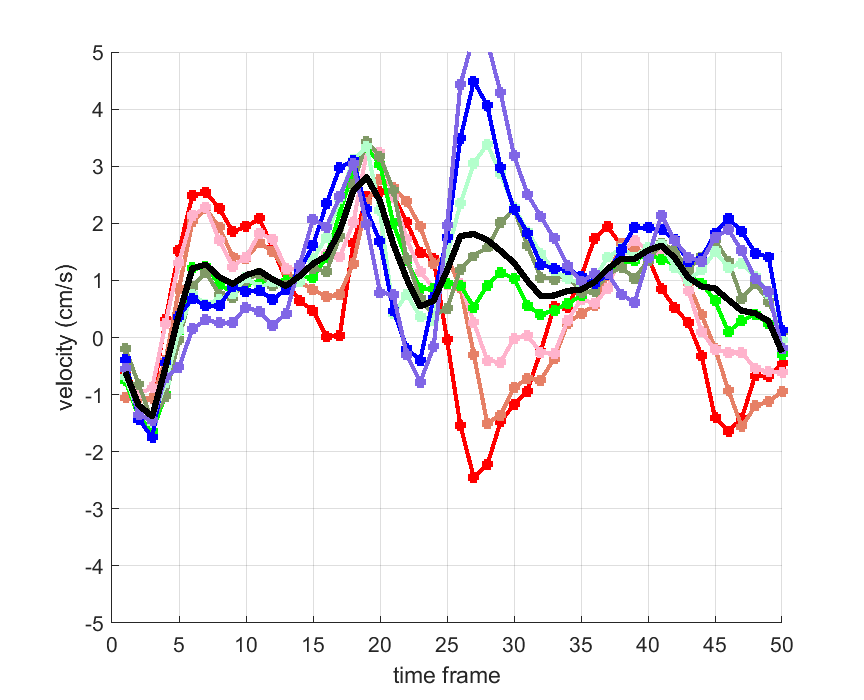

Time courses of the estimated translational component per subject, frame, slice and volume along the 3 velocity directions x, y and z are presented in Fig.6 - Fig.8.